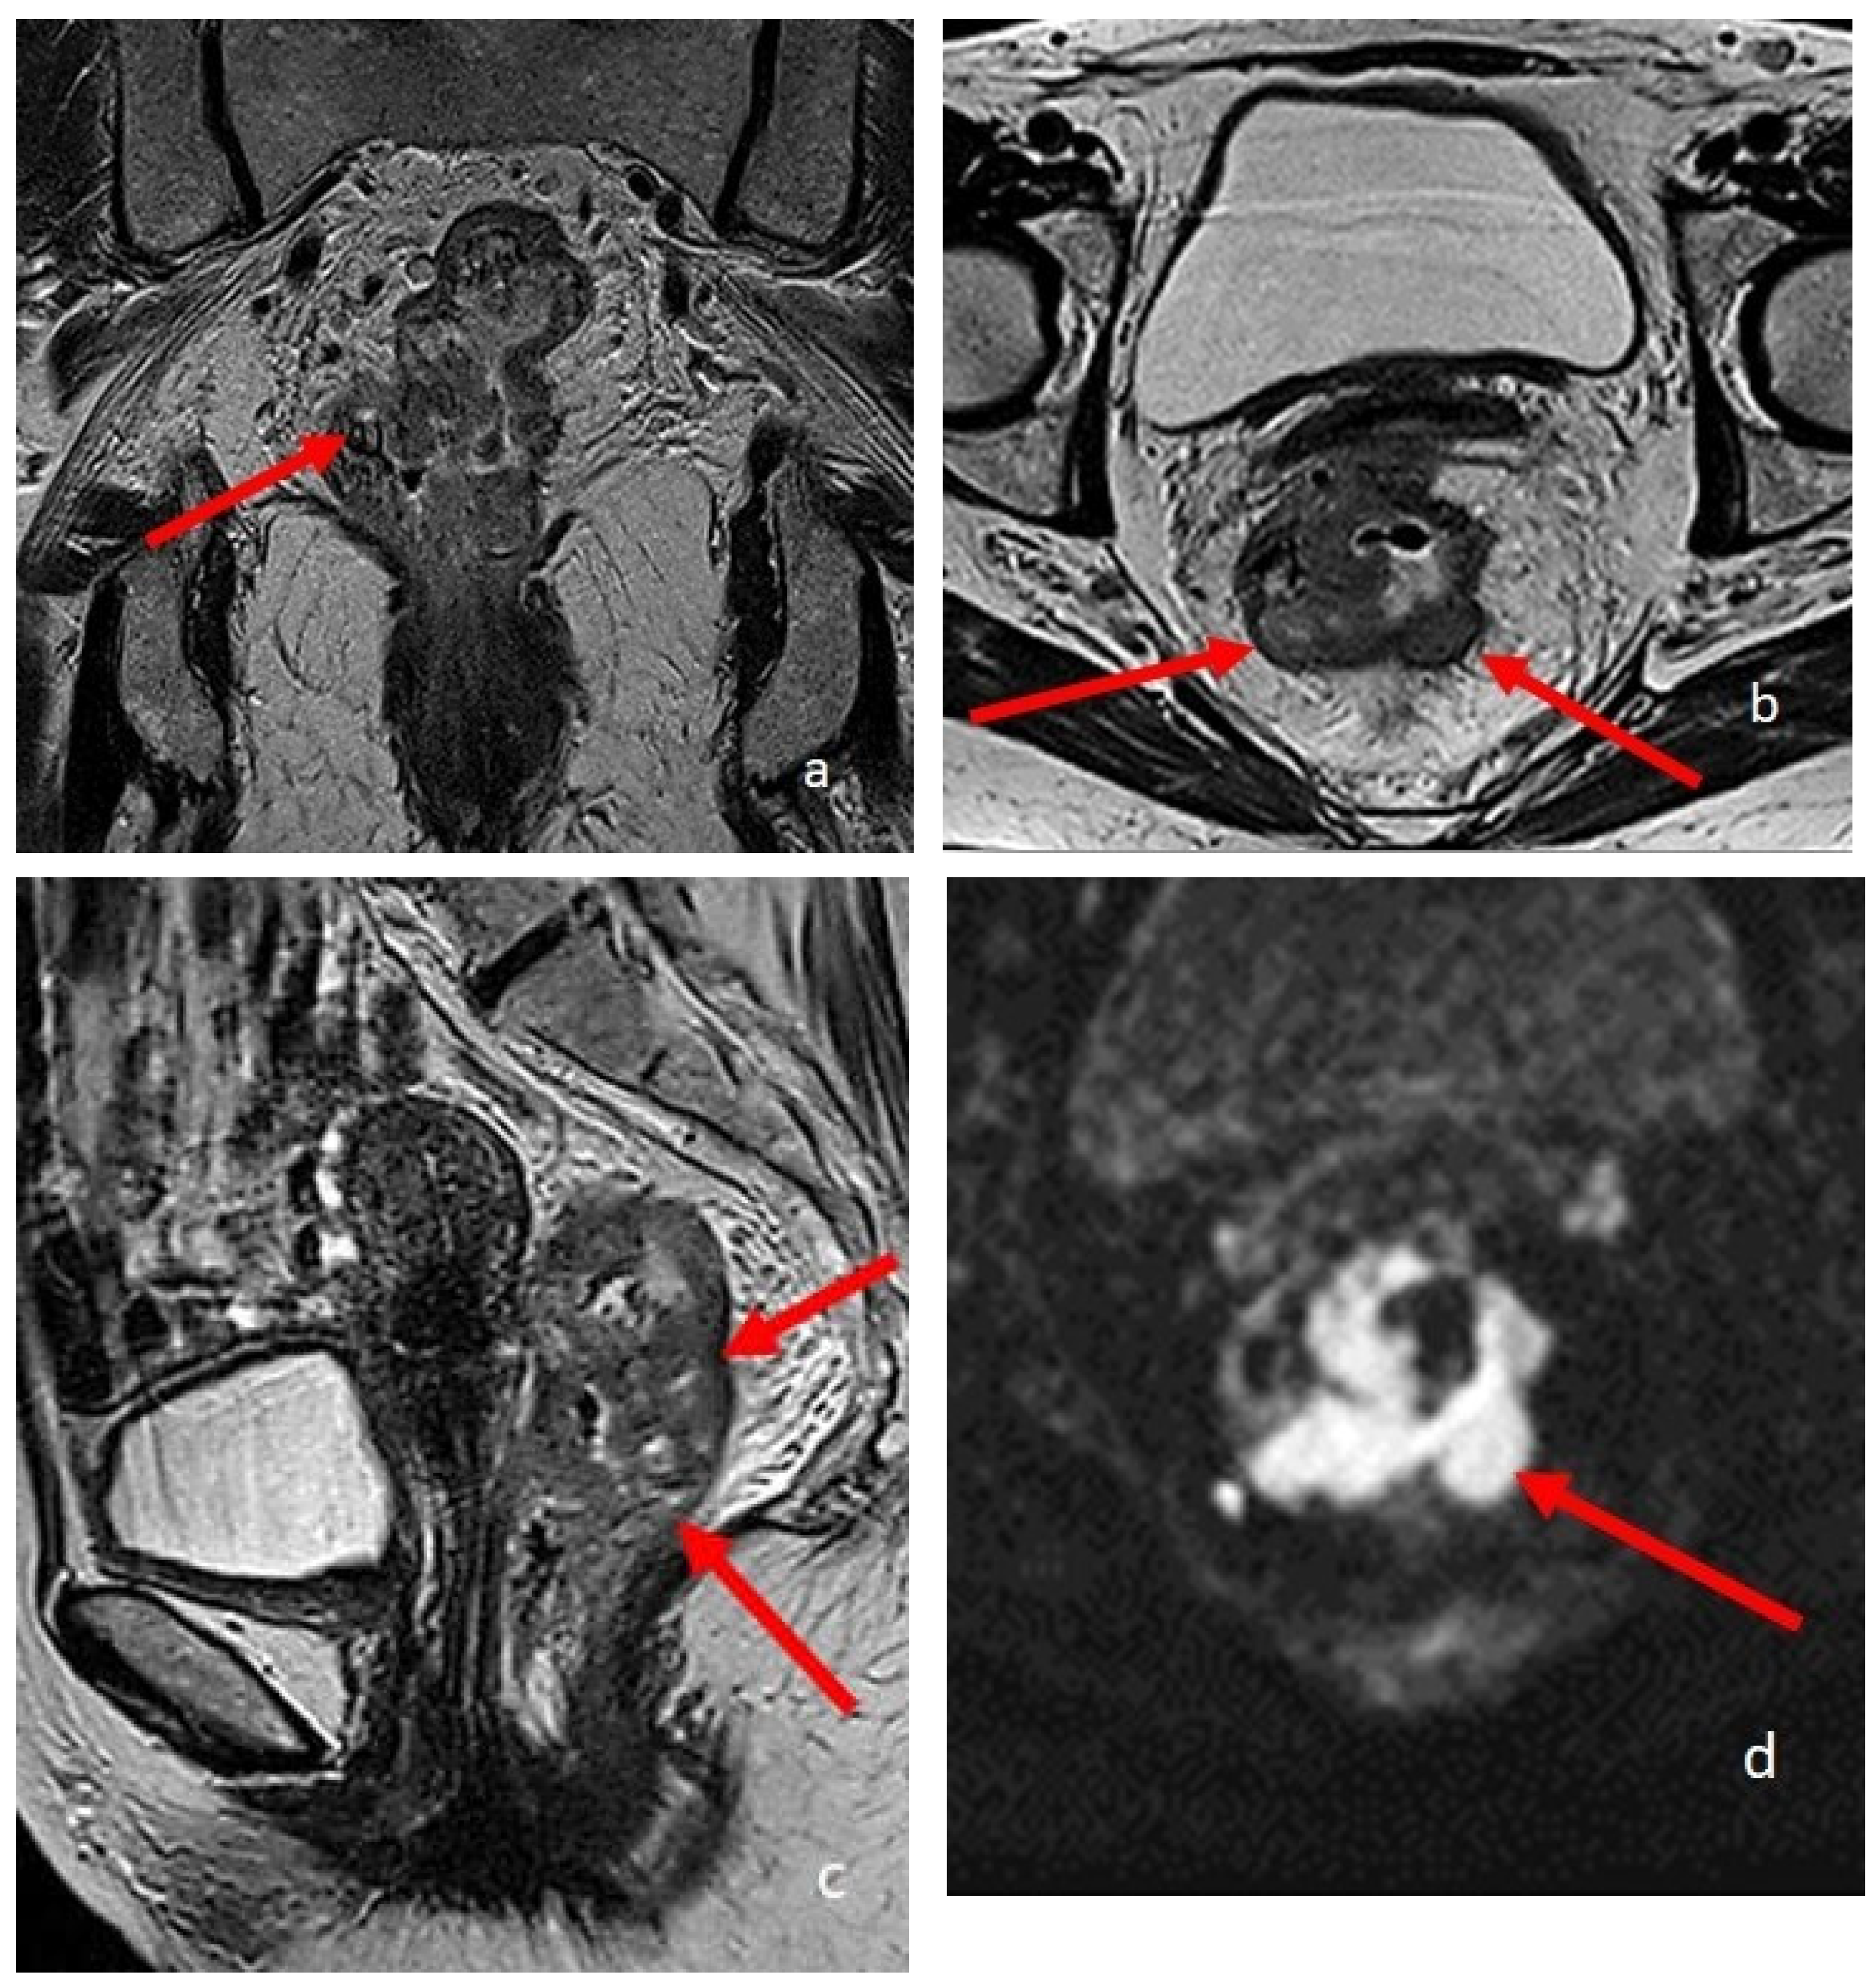

Figure 4.

A 74-year-old patient with rectal cancer. (a–c) are T2-weighted high-resolution images in the coronal, sagittal, and axial planes, respectively. The arrows point to the pathological parietal thickening of the walls of the rectum. (d) is an Axial DWI b1000 image.